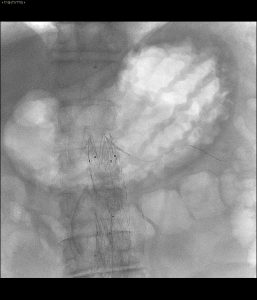

- Controllo che mostra arteria renale non opacizzata

La Sfida Intra-procedurale: L’Occlusione Renale Inaspettata

Durante la procedura è emersa un’insidia improvvisa: l’occlusione dell’arteria renale sinistra. In questi momenti, la capacità di reazione del team e la versatilità degli strumenti endovascolari sono determinanti.